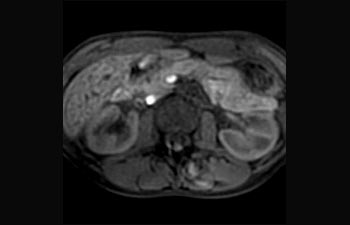

Sehen Sie selbst, was die ersten Nutzer von Ingenia Prodiva 1.5T über ihre Erfahrungen mit dem System und dessen Auswirkung auf ihre radiologische Praxis berichten.

Finden Sie die richtigen klinischen Applikationen für Ihre Anforderungen

1 Basierend auf einer internen Studie zum Vergleich des Workflows mit einem Achieva System 2 ComforTone ist ab Q4 2017 für den Prodiva 1.5T erhältlich. 3 Basierend auf einer internen Vergleichsstudie mit dem Arbeitsablauf des Achieva MRT-Systems bezüglich einer Mischung aus Gehirn-, Wirbelsäulen-, MSK- und Körperuntersuchungen 4 Normaler Betrieb ist definiert als eine typische Untersuchung mit ununterbrochener Verfügbarkeit von Strom und Magnetkühlung und ohne Wartungsmassnahmen. 5 Abhängig von den vertraglichen Ansprüchen und der Verfügbarkeit 6 „Andere MR-Systeme“ bezieht sich hier auf Ganzkörper-MR-Systeme mit 60 cm und 1,5 T.